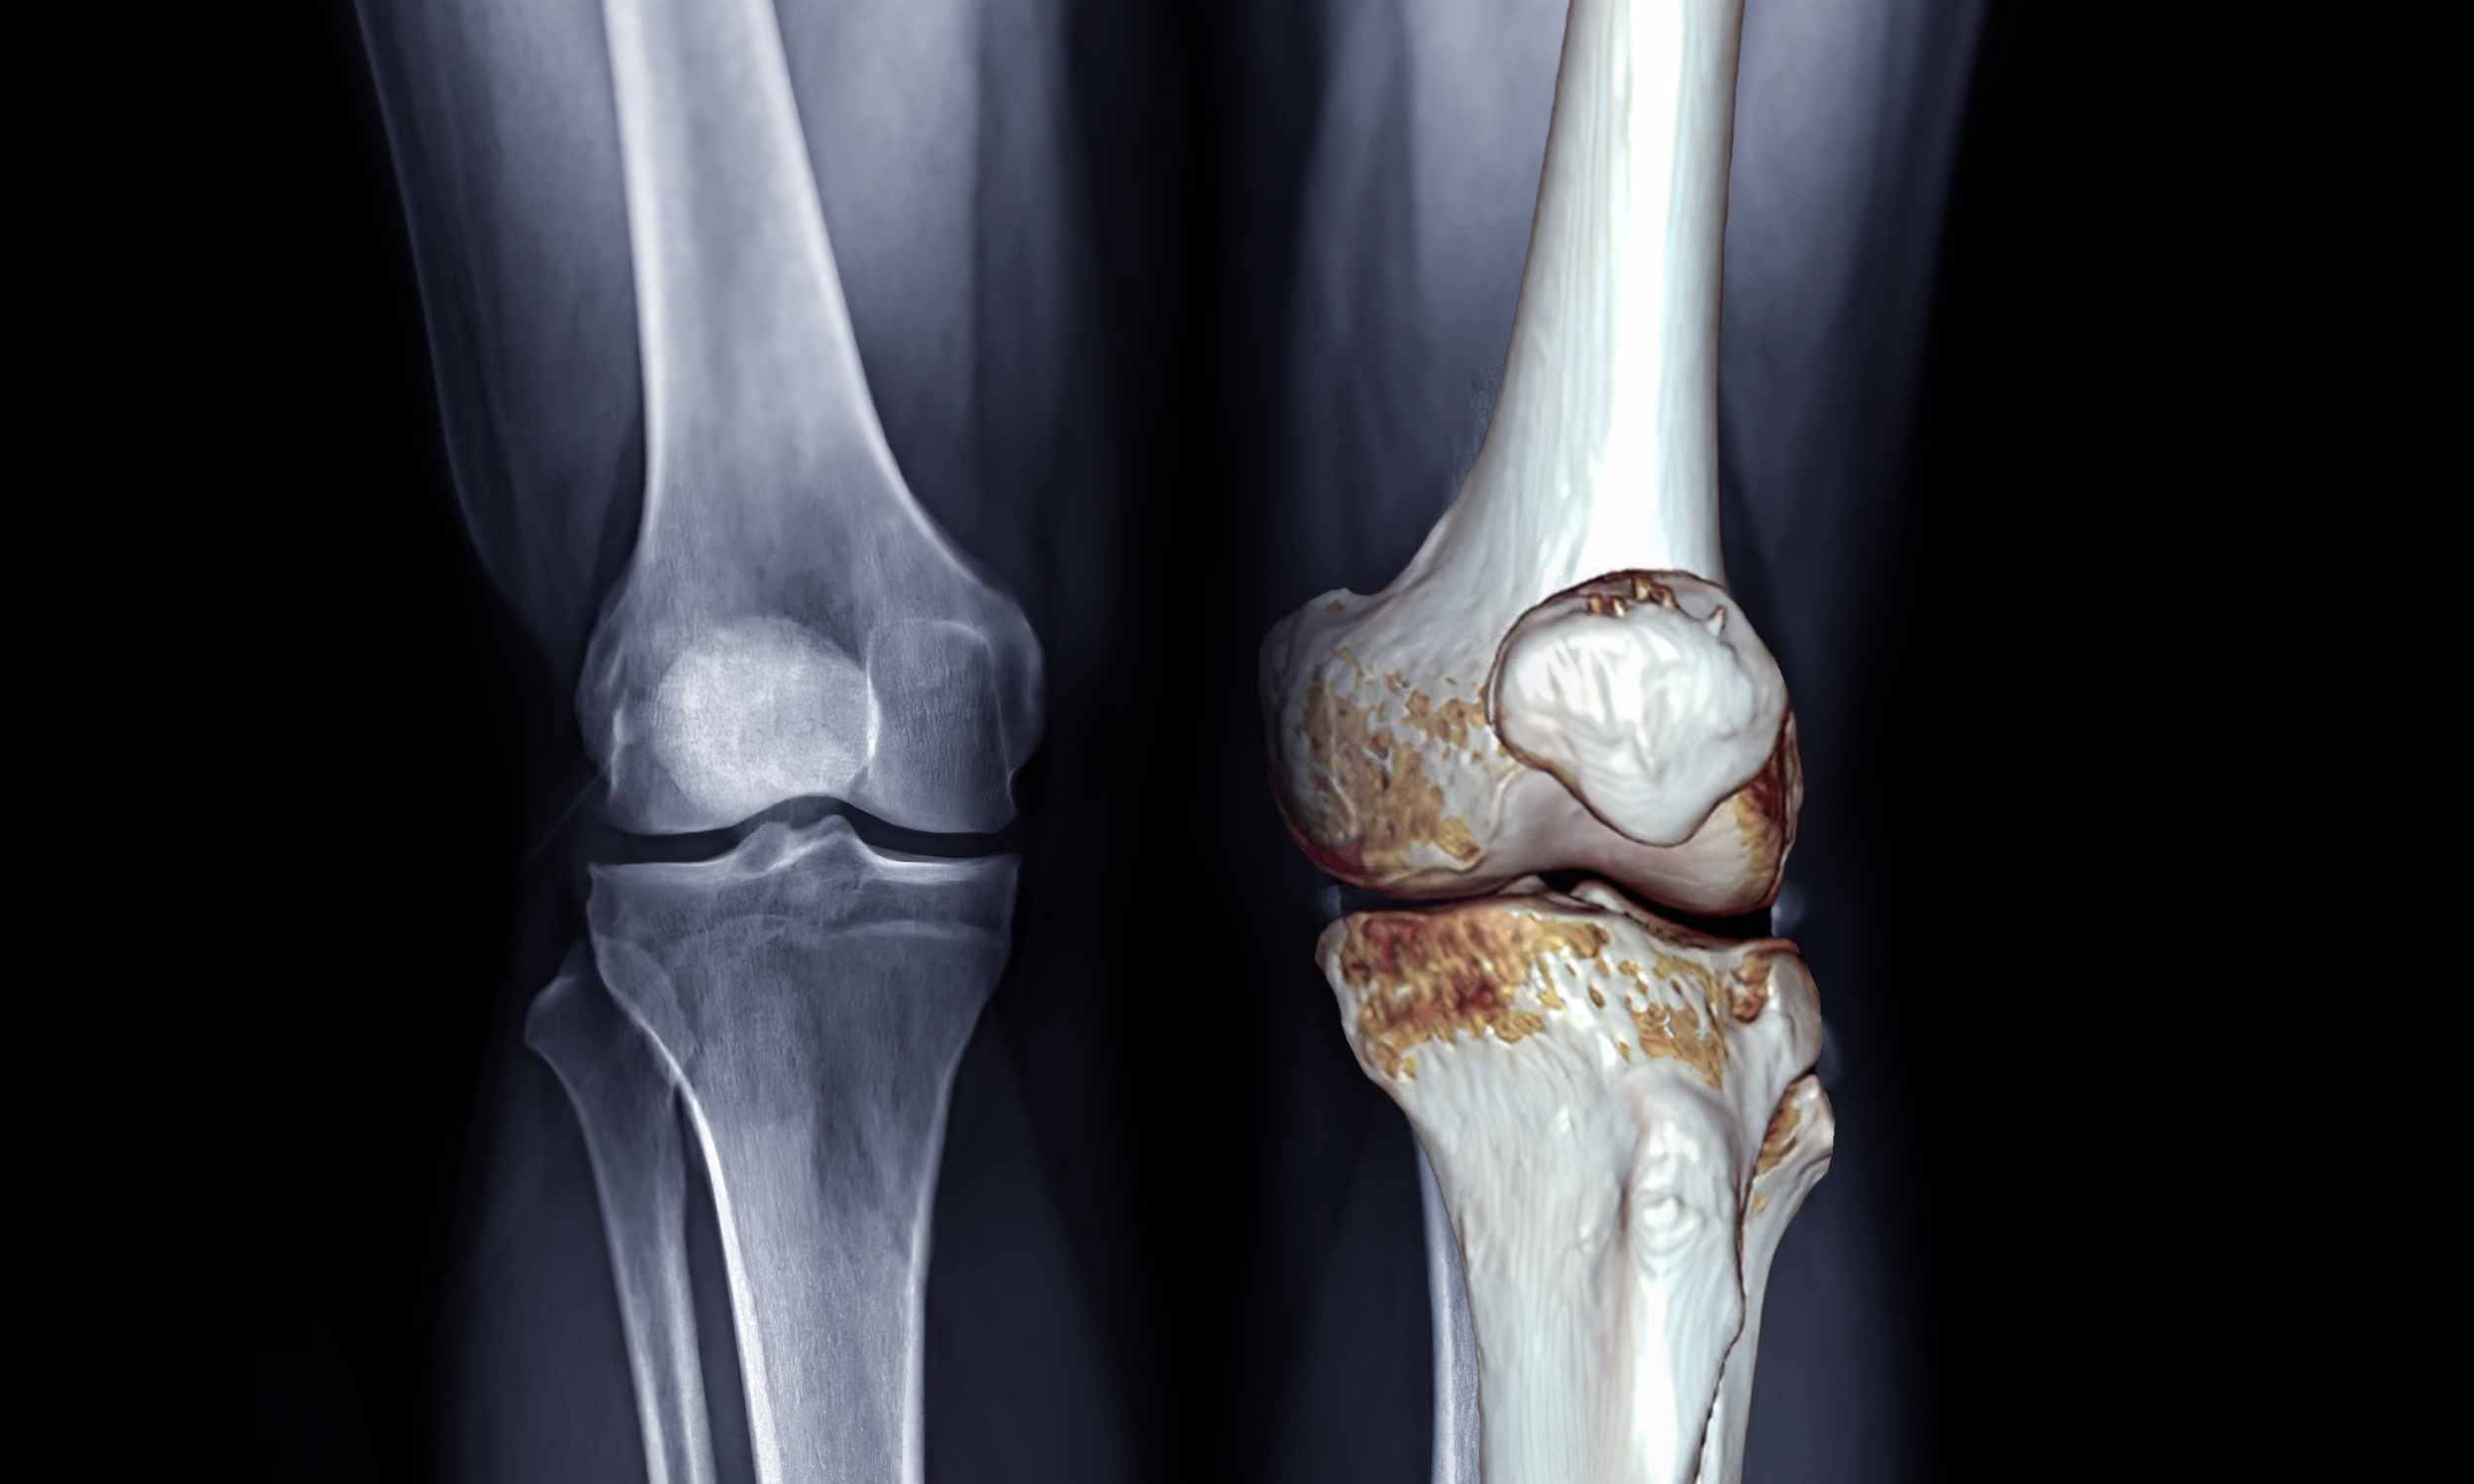

Most people with osteoarthritis, a joint disease that slowly damages cartilage and limits movement, are told to manage pain with pills.

How braces shift the load

A knee brace for arthritis is usually a rigid or semi rigid device that wraps around the joint. By changing how body weight passes through the knee, the brace can take pressure off the worn compartment and reduce irritation of sensitive tissues.

Clinical research on unloader braces, rigid supports that relieve pressure from one side of the knee, shows clear short term pain relief. Several trials also report better function and longer walking distance when people use these braces consistently.